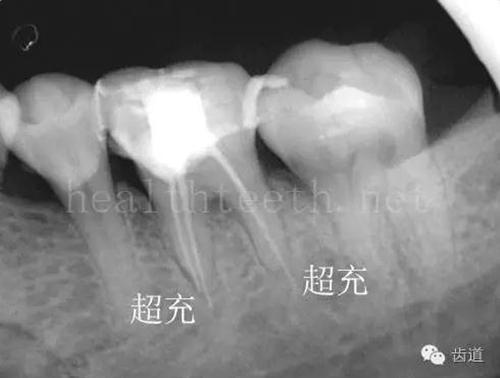

不良的根管充填治療

78.jpg